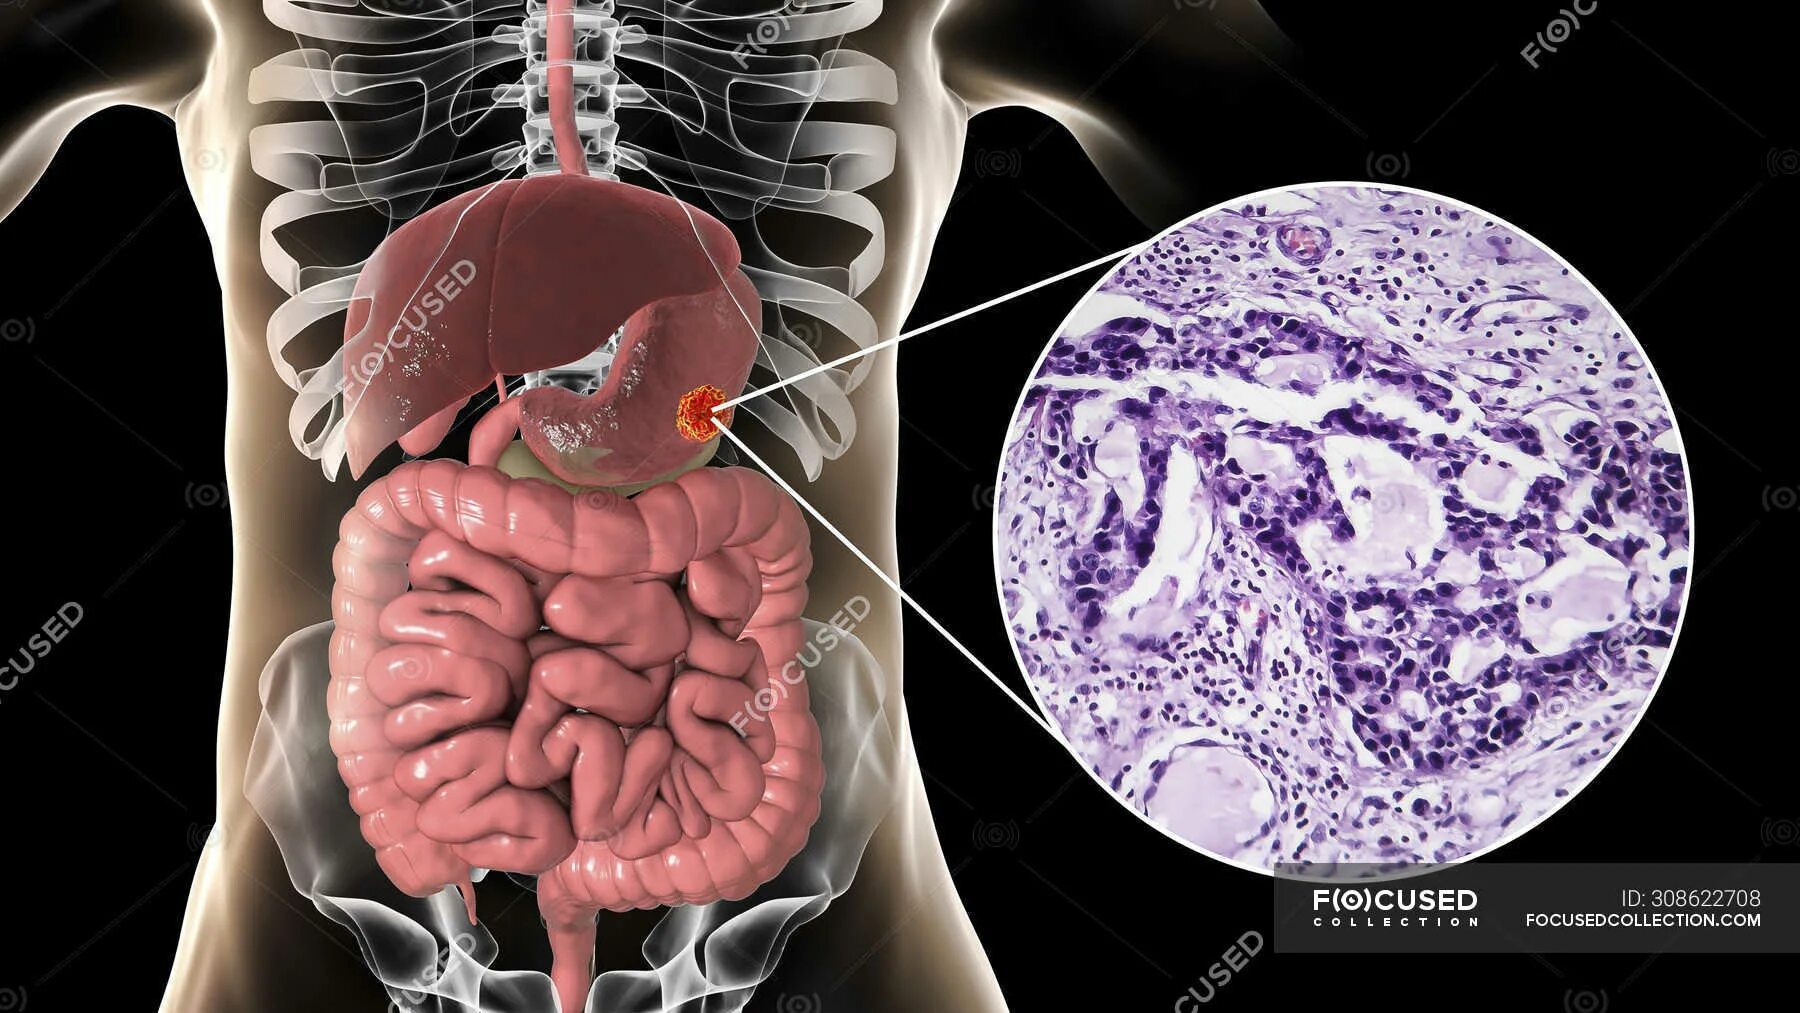

Метастазы в поджелудочную железу прогноз